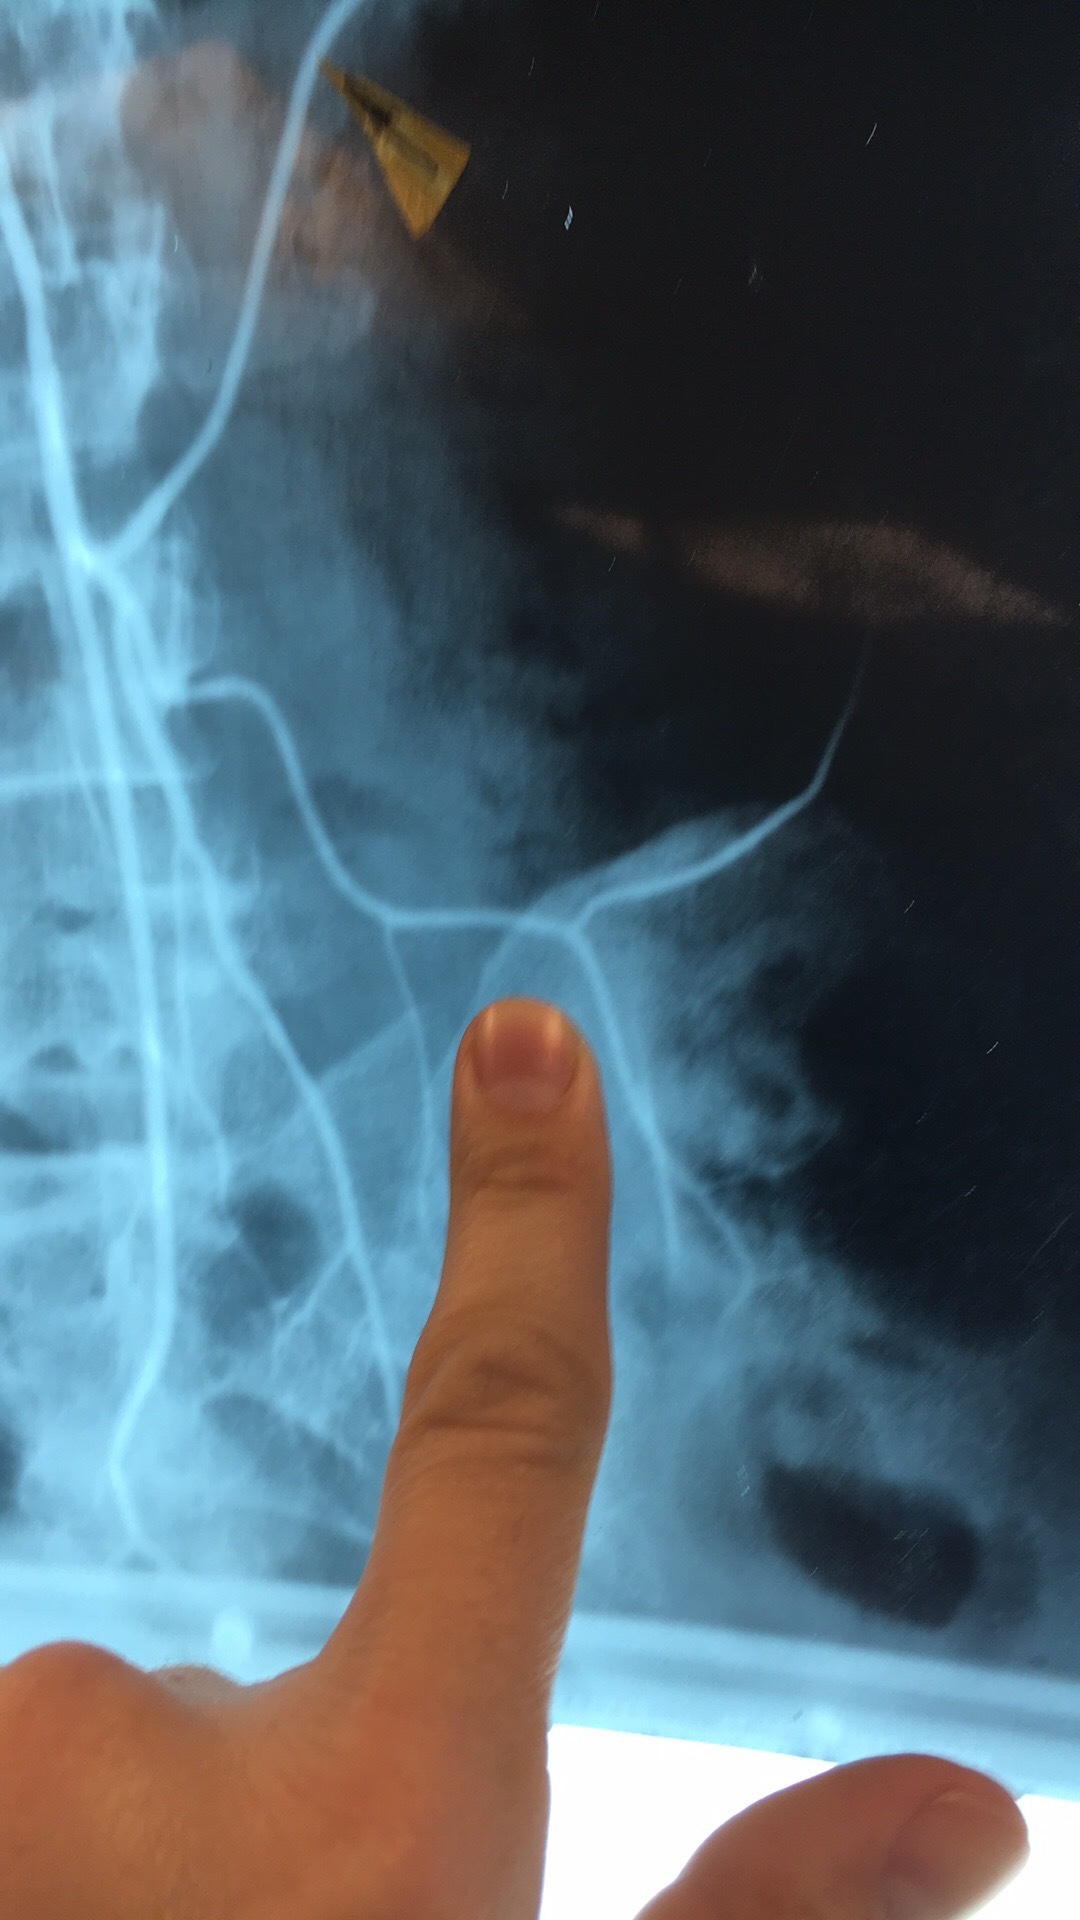

Which artery? What are the branches?

Celiac Trunk. Left Gastric Art, Common Hepatic Prtery, and Splenic Art